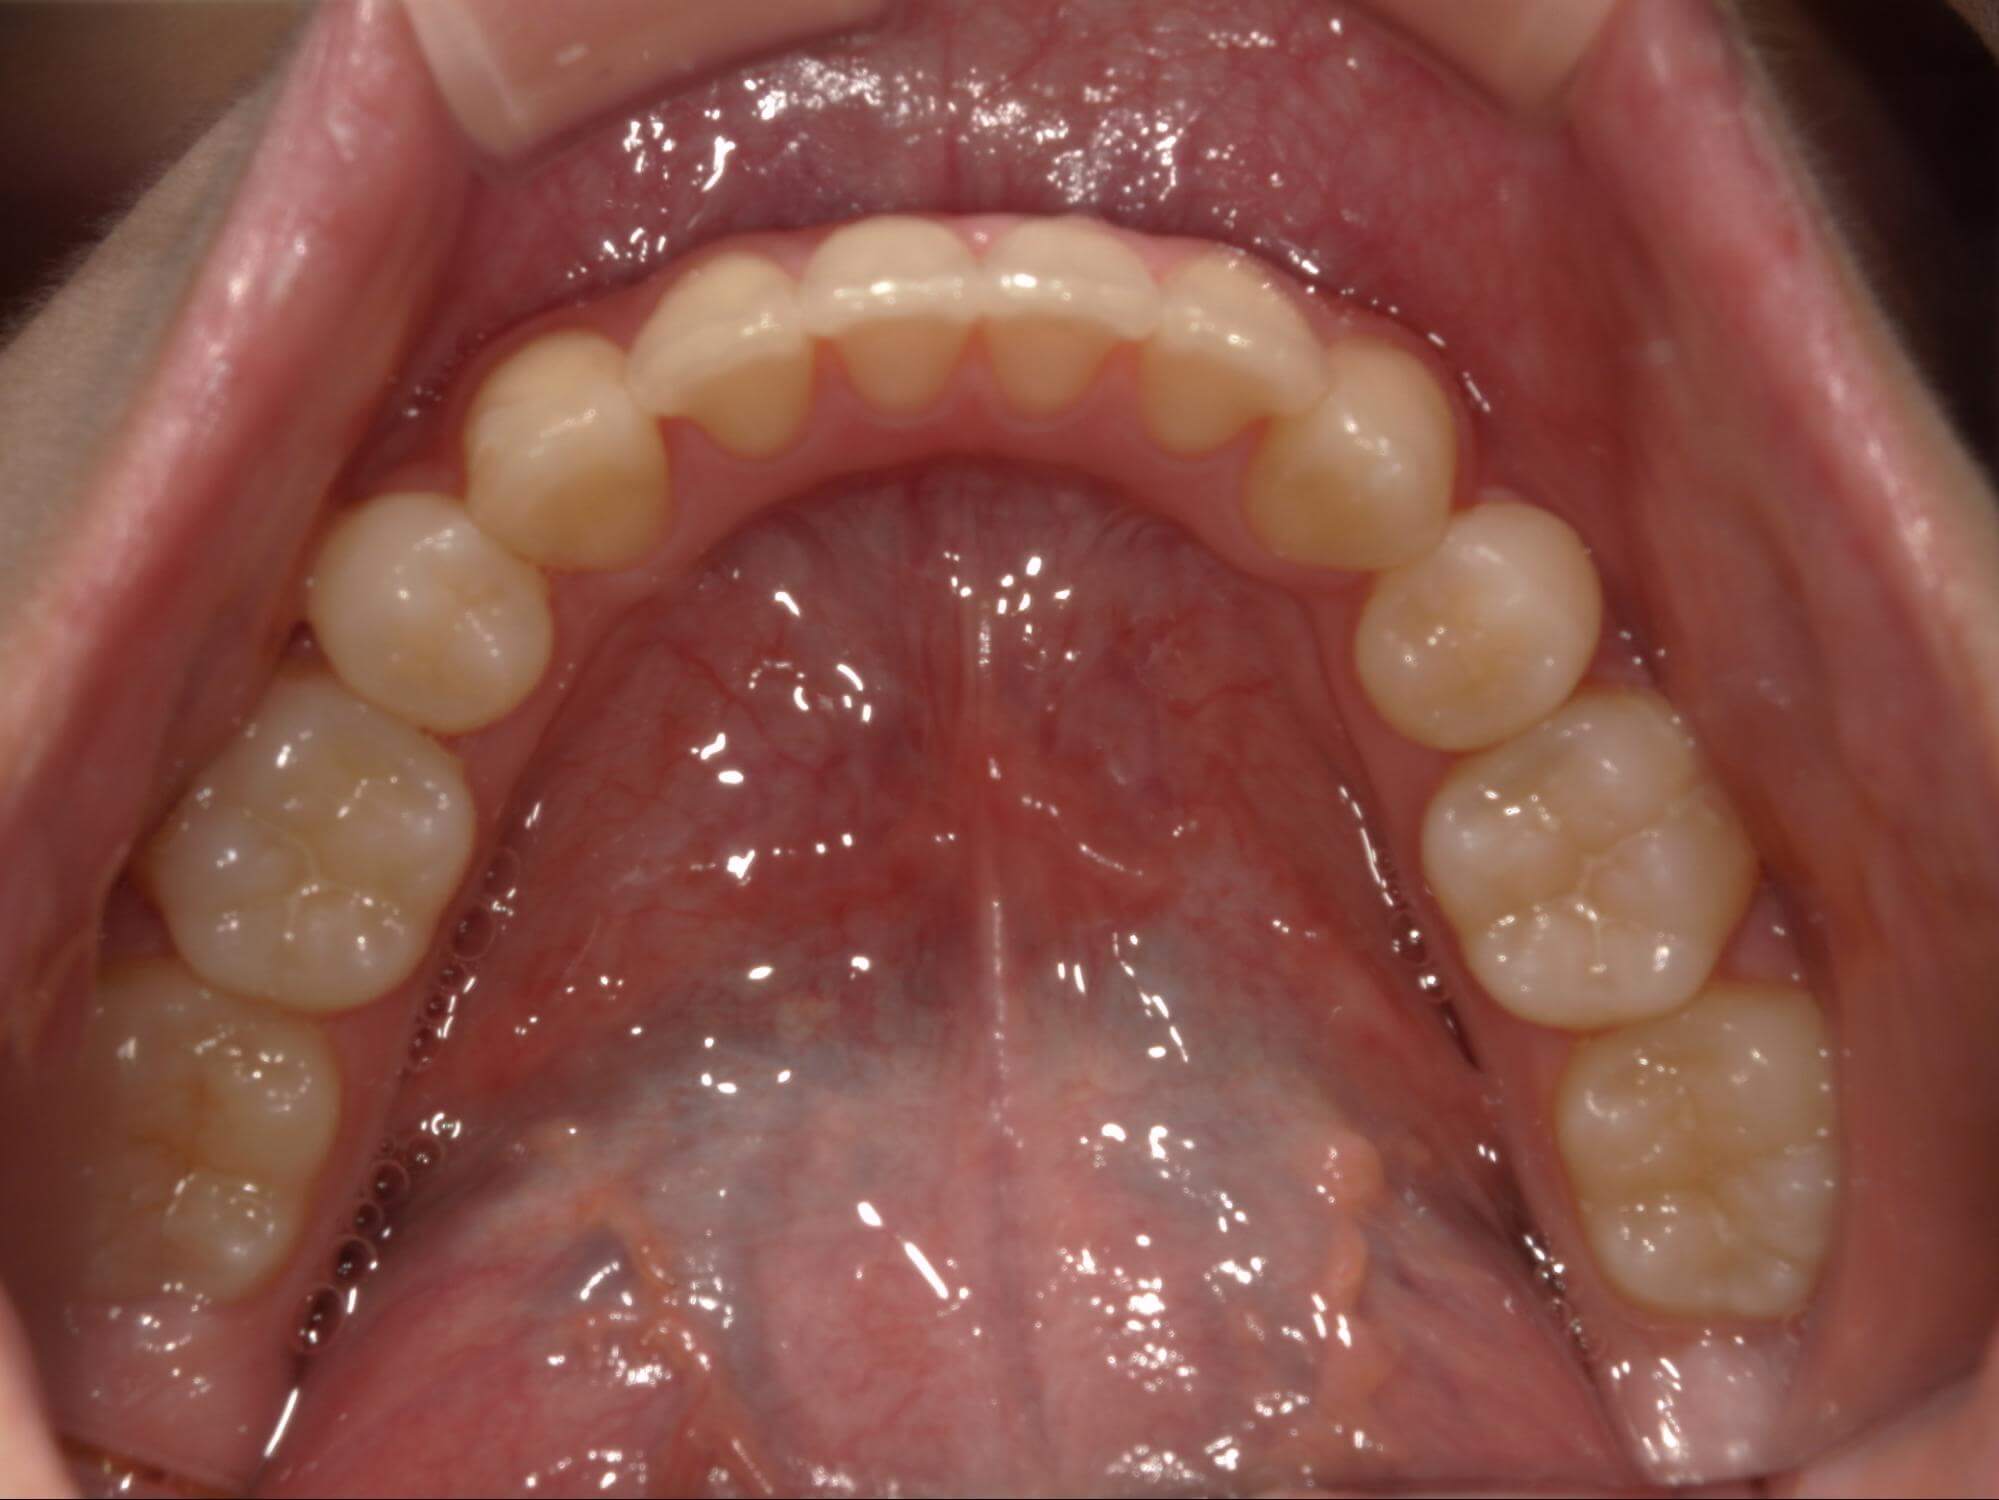

| 年齢・性別 | – |

|---|---|

| 主訴 | 叢生が気になる |

| 治療期間・回数 | 1年9ヶ月 |

| 費用 | 1,011,000円 |